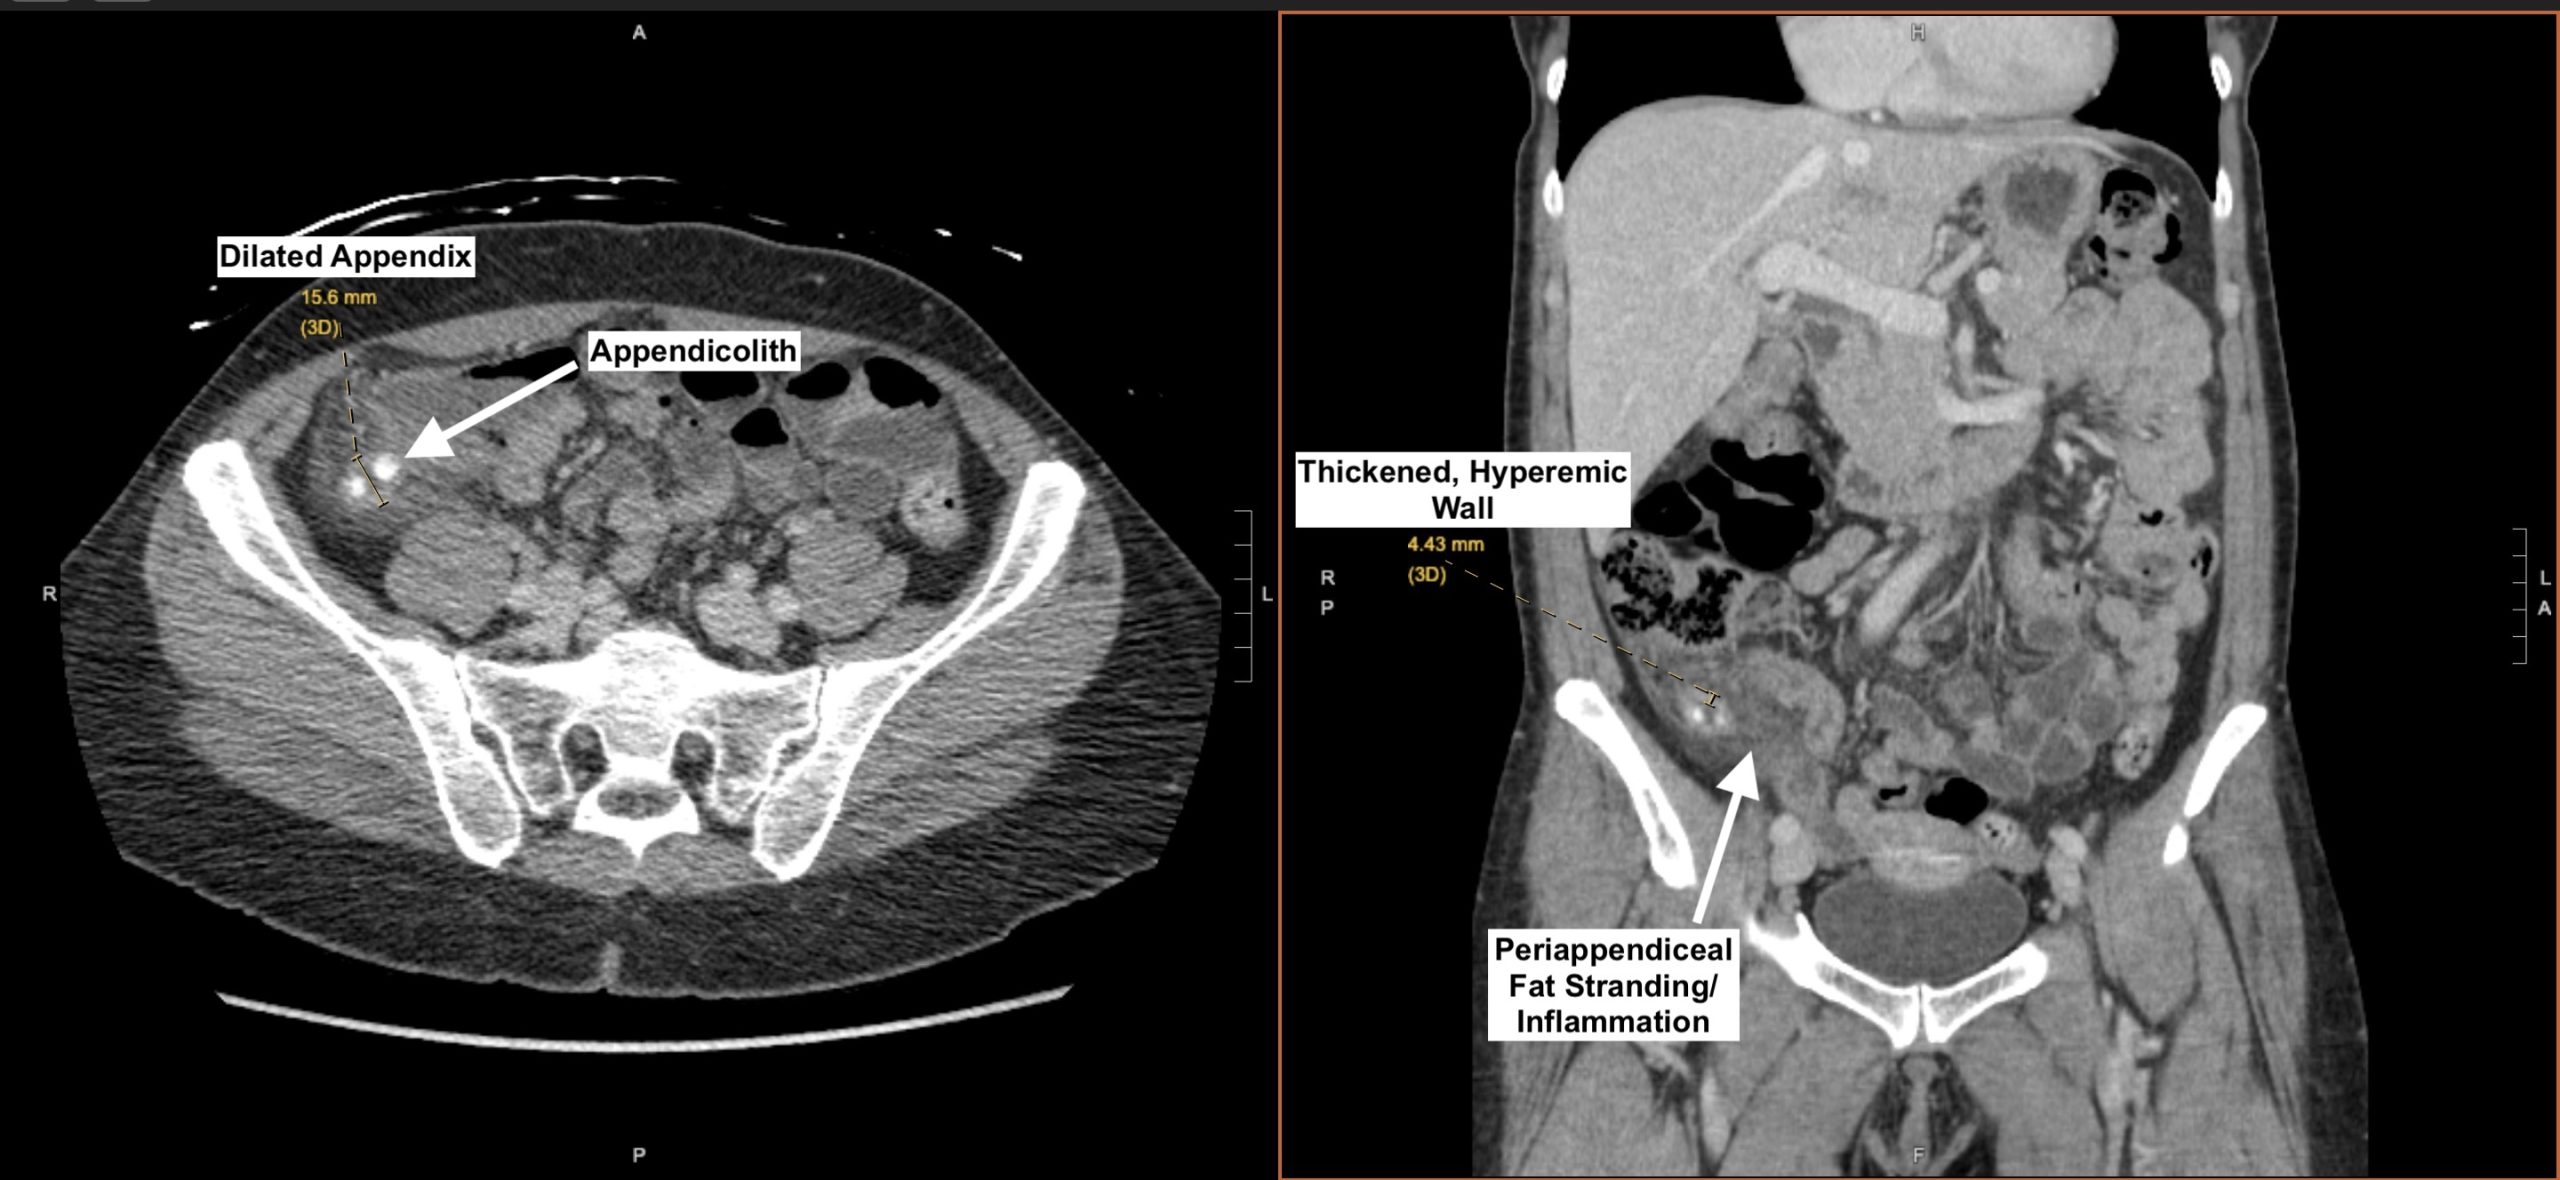

📌 Remember: APPENDIX - Anesthesia (right lower quadrant), Pain (periumbilical → RLQ), Position (flexed hip), Elevation (WBC >10,000), Nausea (early symptom), Defense (McBurney's point), Inflammation (CRP >3mg/dL), X-ray (CT sensitivity 95%)

> 💡 **Master This**: **Rovsing's sign** (RLQ pain with LLQ palpation) has **68%** sensitivity for appendicitis, while **psoas sign** (pain with hip extension) suggests **retrocecal appendix**. **Alvarado score ≥7** has **92%** sensitivity, but **CT remains gold standard** with **95%** sensitivity and **99%** specificity.

- **CT with IV contrast**: **first-line** for **suspected appendicitis** (>30 years)

+ **CT sensitivity**: **appendicitis 95%**, **cholecystitis 90%**, **pancreatitis 85%**